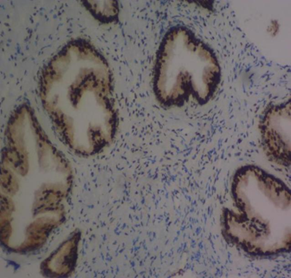

The mean percentage reactivity of immunohistochemistry biomarkers was presented in Figure 1. The results showed a gradual increase in percentage reactivity in MLH1 and MSH2 from BPH to prostate cancer. Figure 2 displayed Hematoxylin and Eosin-stained sections of control tissue samples at x100 and x400 magnification, respectively. Figure 3 presented Hematoxylin and Eosin-stained sections of MLH1 expression in BPH and PC at x100 and x400. The result of (A) showed mild expression of MLH1 in benign prostatic hyperplasia at x100, (B) exhibited moderate expression of MLH1 in prostate cancer at x100, (C) showed mild expression of MLH1 in benign prostatic hyperplasia at x400, and (D) demonstrated moderate expression of MLH1 in prostate carcinoma at x400. Figure 4 displayed Hematoxylin and Eosin-stained sections of MSH2 expression in BPH and PC at x100 and x400. The results of (A) showed mild expression of MSH2 in benign prostatic hyperplasia at x100, (B) displayed moderate expression of MSH2 in prostate carcinoma at X100, (C) illustrated mild expression of MSH2 in benign prostatic hyperplasia at x400, and (D) demonstrated moderate expression of MSH2 in prostate carcinoma at x400.

Figure 3 Haematoxylin and Eosin-stained sections of MLH1 expression in BPH and PC at x100 and x400 respectively. (A) MLH1 in benign prostatic hyperplasia at x100. (B) MLH1 in prostate cancer at x100. (C) MLH1 in BPH at x400. (D) MLH1 in prostate carcinoma at x40

Figure 4 Haematoxylin and Eosin-stained sections of MSH2 expression in BPH and PC at x100 and x400 respectively. (A) MSH2 in benign prostatic hyperplasia at x100. (B) MSH2 in prostate carcinoma at x100. (C) MSH2 in BPH at x400. (D) MSH2 in prostate carcinoma at